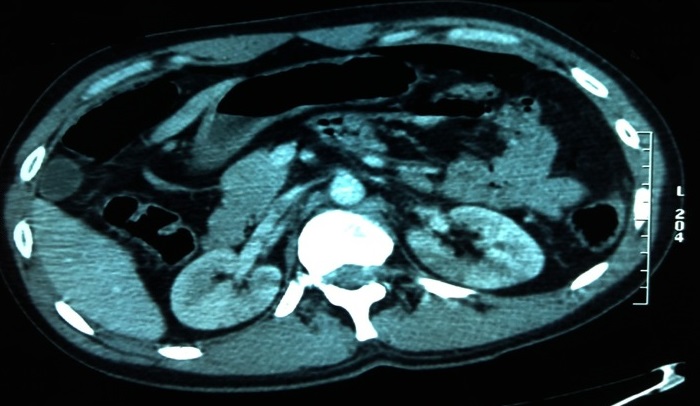

L'infarctus rénal post-traumatique est une complication rarement décrite dans la littérature. Jeune patient de 38 ans sans antécédents pathologiques notables, admis au service des urgences pour prise en charge d'un traumatisme grave suite à un accident de la voie publique par choc direct contre le tableau de bord de voiture avec mécanisme de décélération brutale dans le plan horizontal. A l'admission, le patient était stable sur les plans hémodynamique et respiratoire avec un GCS à 14/15. Un body scanner fait après mise en condition initiale objectivait: une dissection de l'aorte descendante, un hémothoraxà droite, un épanchement péri-aortique, un pneumopéritoine, une fracture-luxation au niveau D4-D5, une contusion splénique, des zones hypodenses triangulaires rénales bilatérales à base périphérique et à sommet central en rapport avec des infarctus rénaux, et une luxation complète de la tête fémorale gauche associée à une fracture de la colonne postérieure. Le bilan biologique revenait sans anomalies et le patient était admis ensuite au bloc opératoire. L'infarctus rénal post-traumatique peut être secondaire soit à une thrombose soit à une dissection du pédicule artériel rénal. Cependant, parmi les patients victimes d'un traumatisme abdominal, 1 à 4% vont avoir des lésions vasculaires rénales. Ces lésions sont classées en: avulsion, lacération, dissection et occlusion de l'artère rénale. Cette dernière entité pose un problème de prise en charge thérapeutique. Sur le plan physiopathologique, ce type de lésion résulte essentiellement de 2 mécanismes: soit une lésion de l'intima secondaire au traumatisme, soit la compression de l'artère rénale contre la colonne vertébrale.